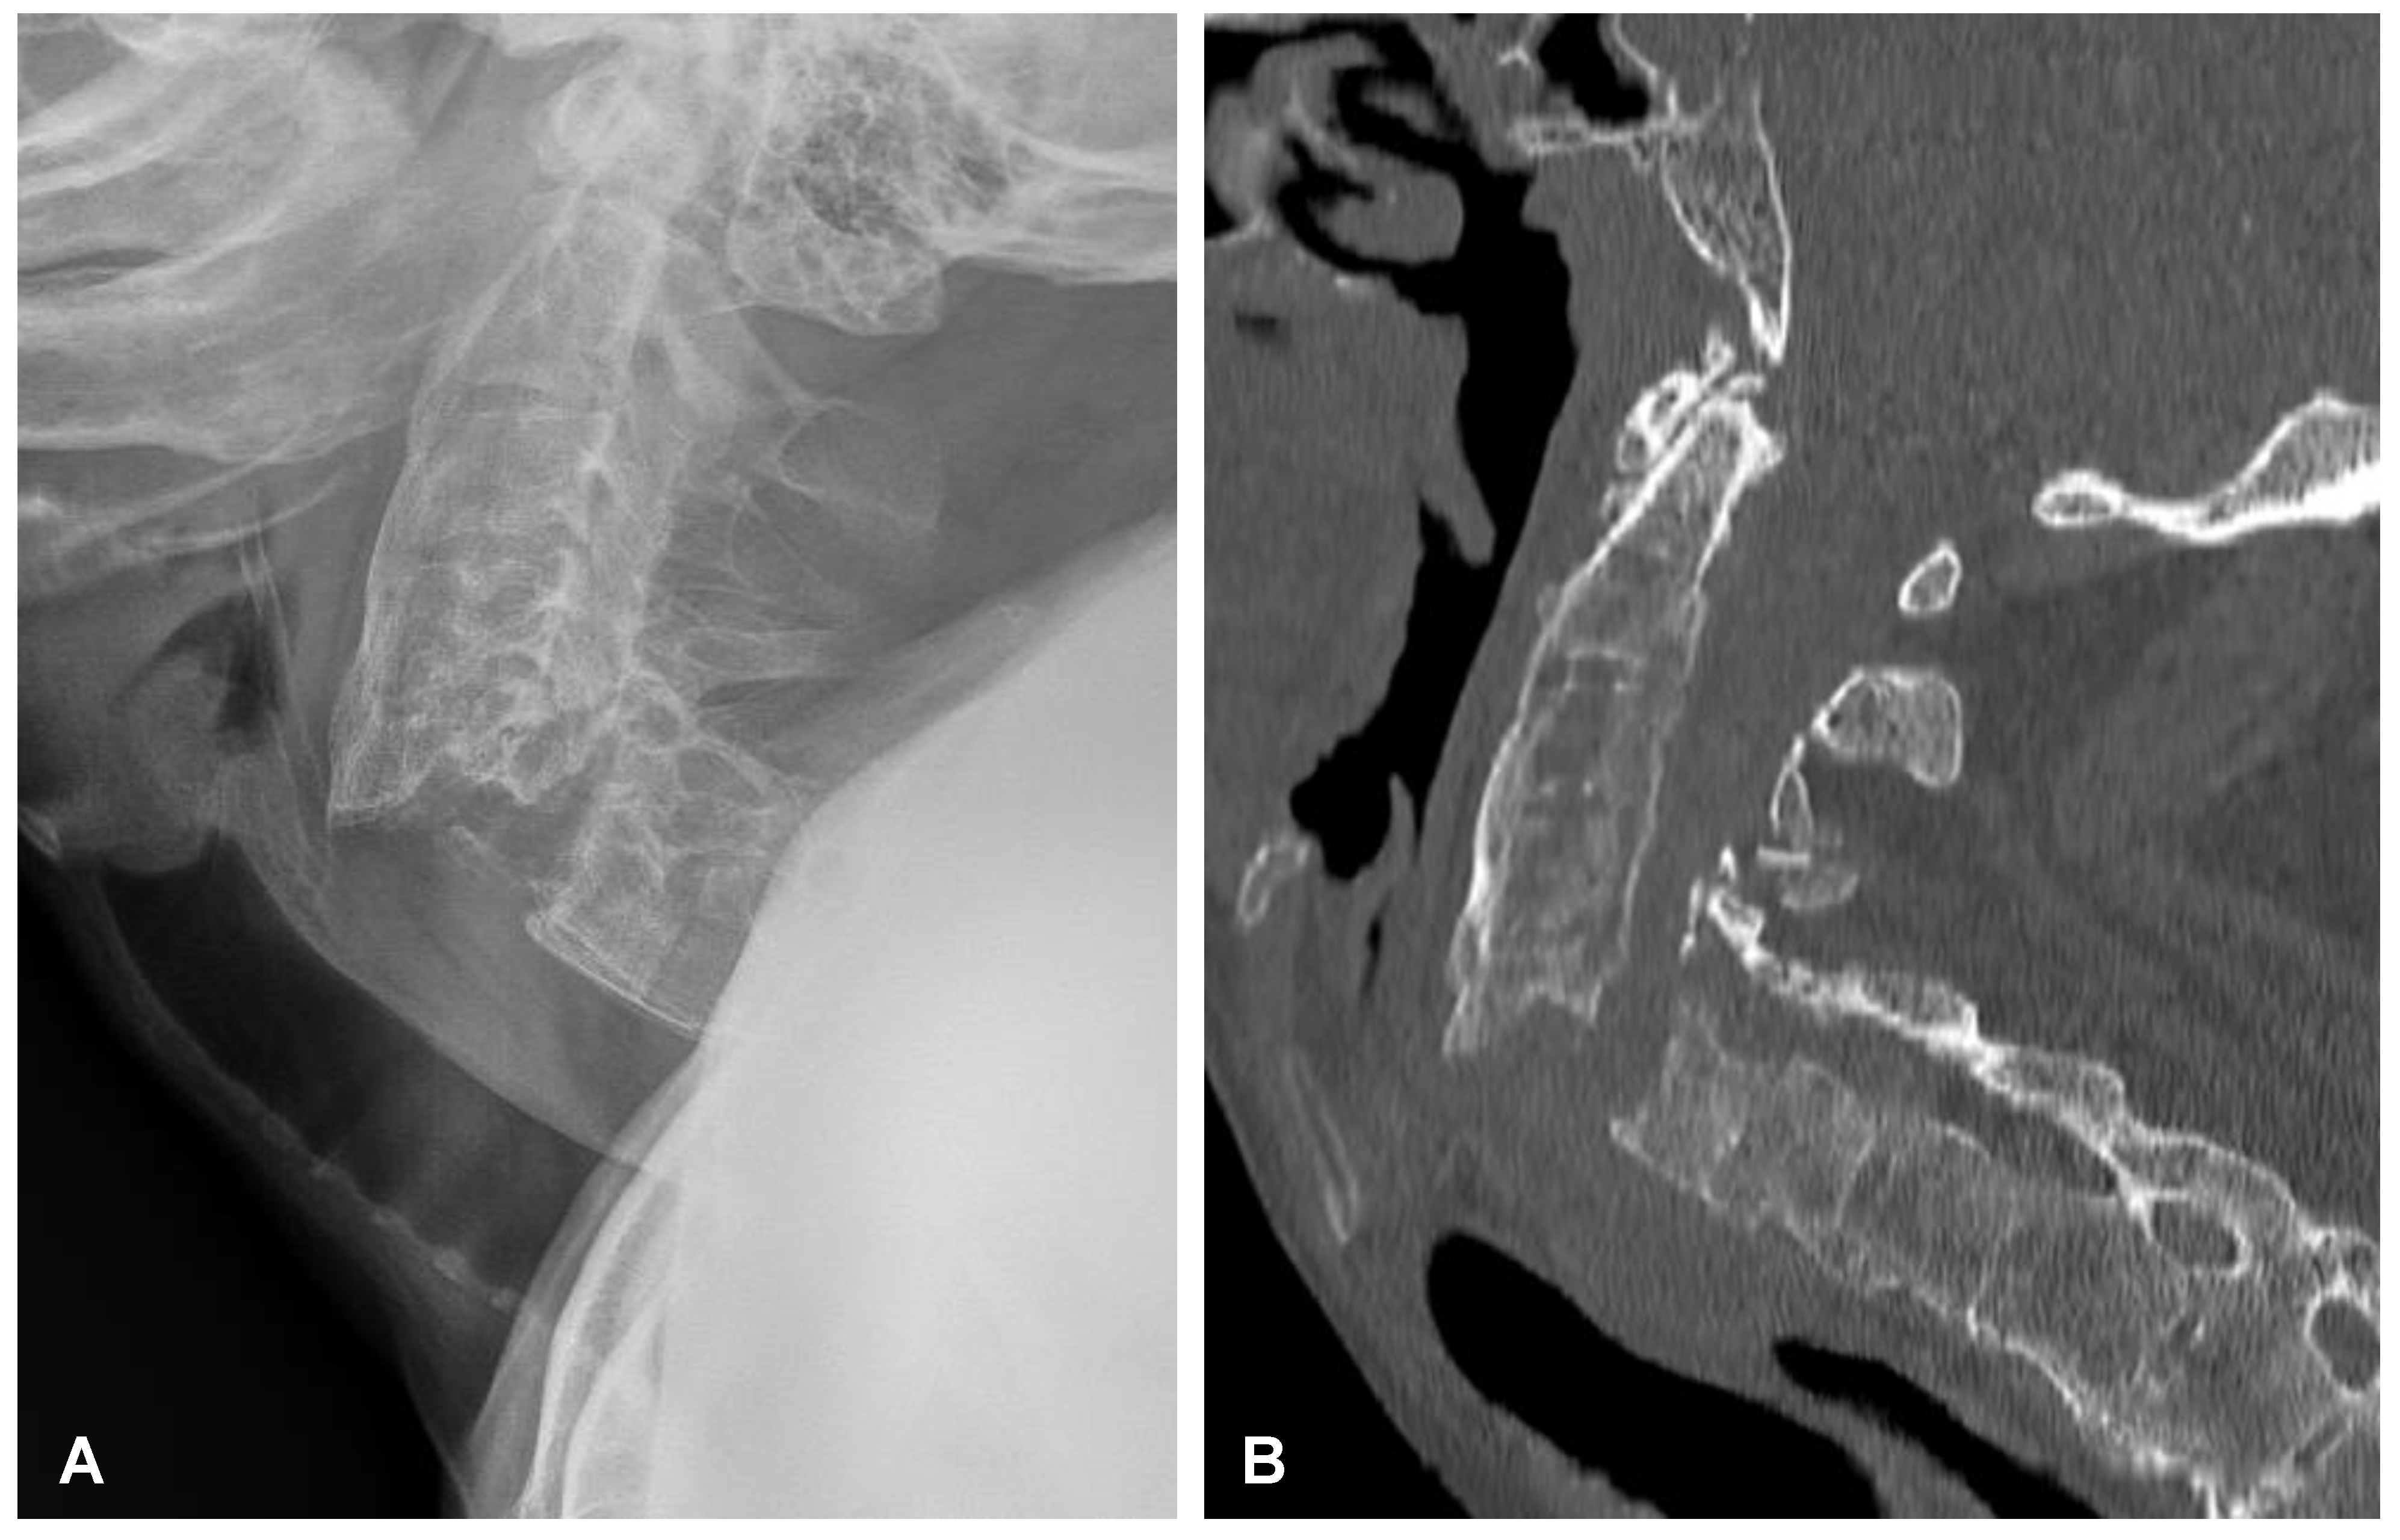

Nevertheless, after 2 years of uncomplicated follow-up, the patient presented again to the hospital with tetraparesis after sustaining a low-energy fall. On admission, the patient was conscious, oriented, and hemodynamically stable. During the examination, the neck was stiff and rigid; movements in the lateral direction and flexion/extension were impossible. The initially performed plain radiograph and CT scans of the cervical spine demonstrated an extension transdiscal three-column fracture at the C5/C6 level, which was morphologically classified as type C according to the AO spine classification (Figure 8). Otherwise, there was no evidence of intracranial trauma. Blood analysis performed on admission revealed the following results: Hb: 12.2 g/dL, PLT: 398 × 109/L, WBC: 12.1 × 109/L, CREA: 0.62 mg/dL.

Figure 8. Preoperative plain radiograph (A) and CT scan (B) of the cervical spine demonstrating unstable extension transdiscal three-column fracture at the C5/C6 level.